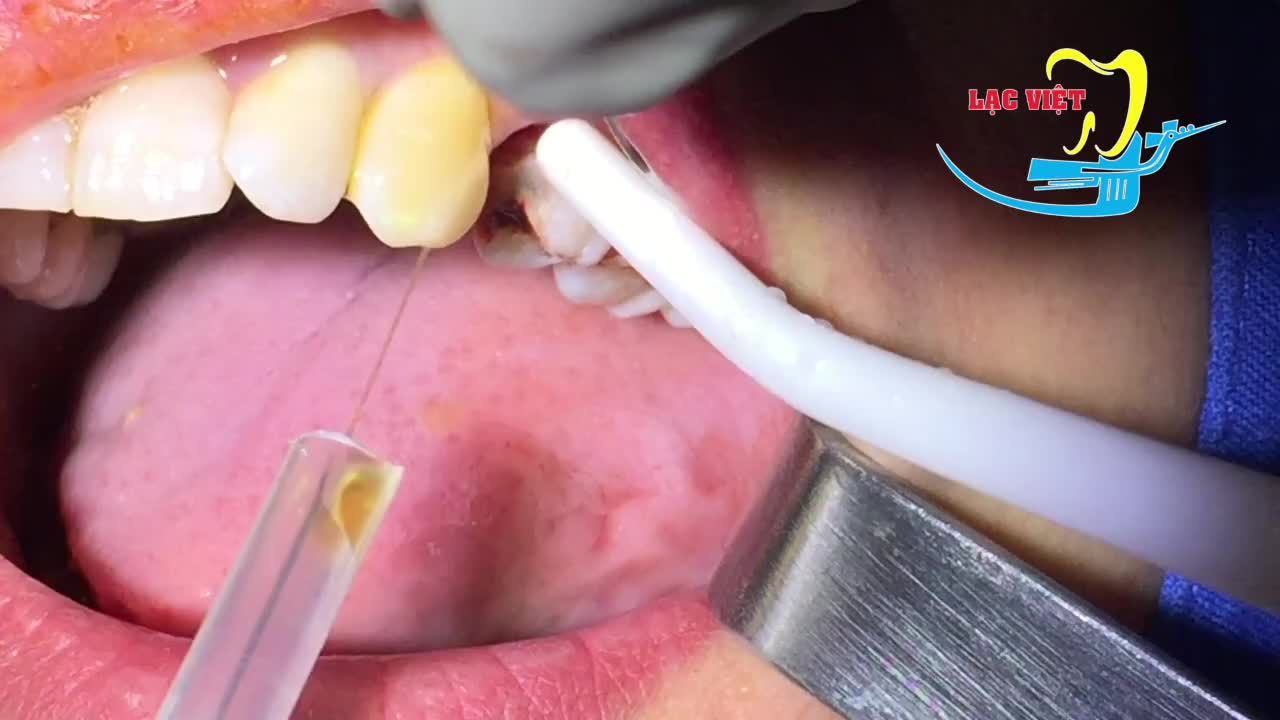

Chú khách hàng đến với Nha khoa Paris trong tình trạng bị sâu răng nặng dẫn đến lung lay và mất nhiều răng. Sau khi thăm khám kỹ lưỡng, bác sĩ Phan Tiến Hoài đã chỉ định cấy ghép 5 trụ implant để khôi phục lại hàm răng, cải thiện chức năng ăn nhai.